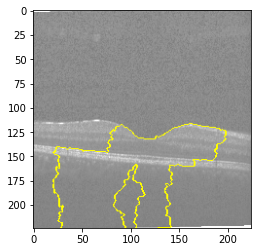

Explanation C

Explanation C

Explanation C

Explanation C

Fig 6, 7, 8 and 9 depicts the visualization of correct predictions by our proposed CNN model where fig 6 is class CNV, fig 8 is class DME, fig 7 is DRUSEN and finally, fig 9 is NORMAL. Here the first photo in every class is the original image. The LIME map of our suggested model’s prediction is shown in image B whereas in image C the positive region is highlighted in specific sections on the original image. For Image D we have increased the number of features from 5 to 10 thus more regions have been predicted as the positive region which is highlighted in green. After increasing the features from 5 to 10, some of the regions are predicted wrongly. The red regions represent the output of incorrect prediction. The following image represents the Grad-CAM heatmap highlighting the regions with our model’s prediction.